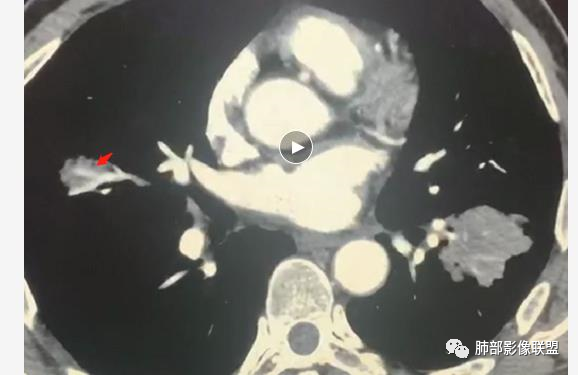

病变分布特点,胸膜下,叶间胸膜下为主,呈大小不等结节级团块影,部分病灶内见支气管影,病灶收缩不明显,从分布及慢性发病看,隐球和淋巴瘤都可,补充增强,病灶内见血管穿行,强化不明显,支持淋巴瘤

老年男性,两肺多发结节肿块,胸膜下分布为主,部分支气管进入闭塞,增强扫描有强化,血管穿行无破坏,边缘尚光滑,周围无晕,病灶整体膨隆为主,半年病程,症状逍遥,首先考虑淋巴瘤

棉花糖:双肺多大小不等结节,边缘清楚,无毛刺,浅分叶,胸膜下分布为主,内可见支气管穿行,增强后中等程度强化,病灶内血管走行自然,考虑淋巴瘤,鉴别GPA

内部支气管稍扩张,直达远端,或受压变形、移位

均匀强化

内部血管走形自然,稍纤细

这里似乎稍增粗

4.血管造影征:肿瘤组织浸润引起间质增厚、肺泡壁破坏、肺泡腔充填,而周围充盈血管走行自然,未受肿瘤侵犯。血管造影征